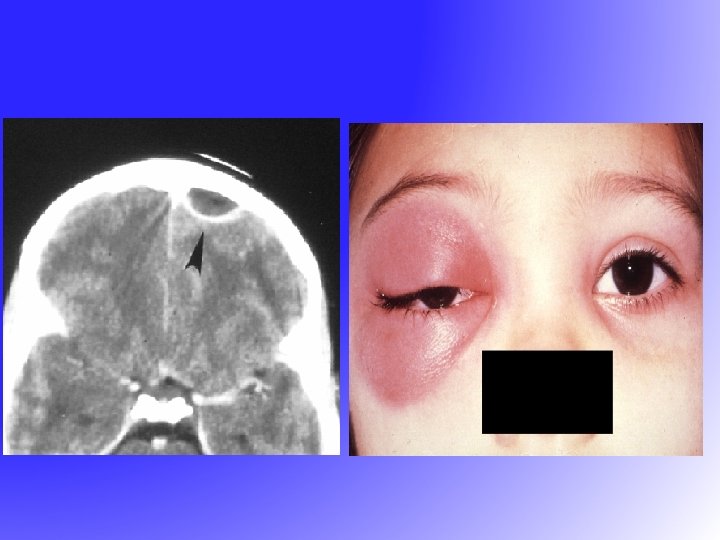

Complications of Sinusitis • Local – Mucocele – Osteomyelitis-Pott’s tumor • Orbital – Orbital cellulitis – Orbital abscess – Cavernous sinus thrombosis • Intracranial – Epidural abscess – Subdural abscess – Intracerebral abscess

Complications of Sinusitis • Local – Mucocele – Osteomyelitis-Pott’s tumor • Orbital – Orbital cellulitis – Orbital abscess – Cavernous sinus thrombosis • Intracranial – Epidural abscess – Subdural abscess – Intracerebral abscess